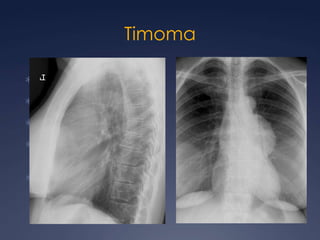

Timoma

TimomaMasa redondaUnilateralContornos lisos o lobuladosCalcificaciones delgadas, lineales en la periferia.Engrosamiento pleural (unilat, masas o  nodular).

TimomaEncapsulada:46-75 U.H.Homogénea u ovalBien delimitada Usualmente asimétricaCalcificaciones focales 25%

Invasivo: 33-50%IrregularOblitera los planos grasos adyacentes (esternón, vasos, pleura, retroperitoneo, abdomen)Timoma invasor

Timoma invasorContraste:Reforzamiento leveHomogéneo Áreas quísticas Áreas de menor densidad

TimomaT1 isointenso al músculo T2 intensidad cercana a la de la grasaSeñal heterogénea sugiere invasión